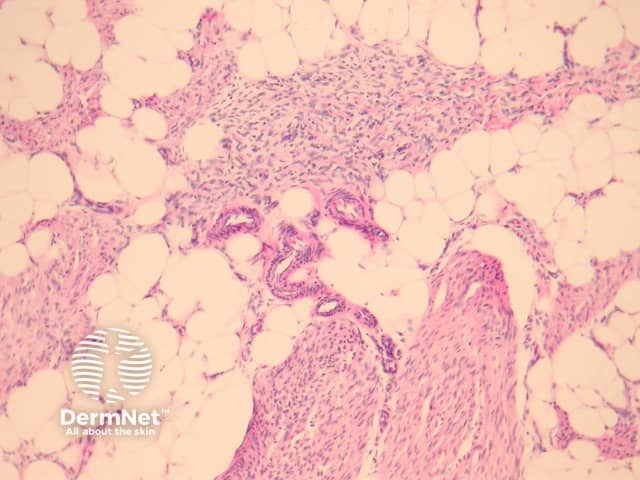

In fibrous hamartoma of infancy, bundles of well-defined thick connective tissue, which branch, interweave, and project into adjacent fat (figure 1). The lesion is composed of three components: adipose tissue, myofibroblasts (best seen in figure 2), and primitive mesenchymal cells (best seen in figure 3). The distinctive primitive mesenchymal tissue organized in distinct whorls, bands, or nests (figure 3). Myxoid change may be prominent.

Figure 1